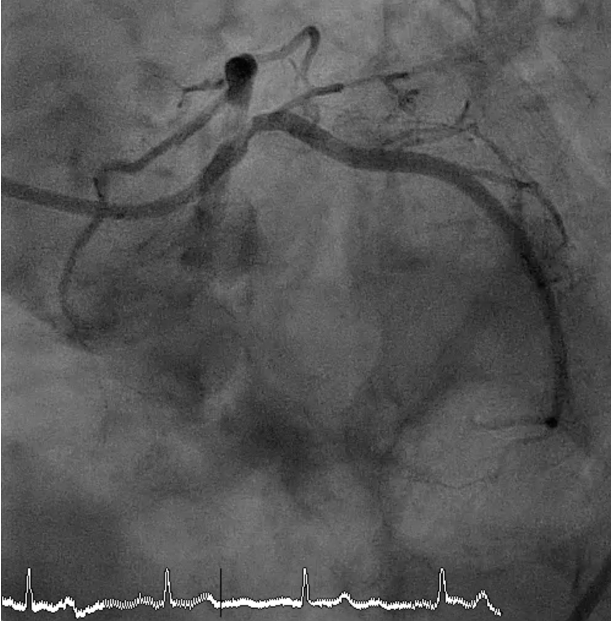

Coronary angiography revealed critical stenosis of the distal left main with calcified nodule at the left main bifurcation (Medina 1-1-1), 90% stenosis at ostial LAD and 90% stenosis at ostial LCx.

A 7 Fr JL 4.0 guiding catheter was engaged into LCA via RFA. We planned to perform PCI at LM bifurcation with Culotte technique. We successful wired to distal LAD using Finecross microcatheter with Conquest Pro guidewire (Failed using Sion blue, Fielder XT and Gaia Next2 guidewires). The microcatheter could not pass LAD lesion. Successfully passed the lesion using Tornus microcatheter. Then we exchanged RotaWire Floppy wire. Rotational atherectomy was done at LM-proximal LAD with Burr 1.25 mm at 180,000 rpm total 2 runs and step up Burr to 1.75 mm at 180,000 rpm total 2 runs for further debulking. Then we wired to LAD with Sion blue and LCx with Sion guidewires. IVUS was performed in LM, LAD and LCx. IVUS from LM-LAD showed eruptive calcified nodules with cracked calcific plaques and reverberation with MLA 2.86 mm2. IVUS from LM-LCx showed MLA 4.6 mm2. We prepare the lesion LM-LAD with non-compliant 4.0/15 mm balloon at 20 atm. A 4.0/18 mm stent was deployed from LM to LAD then re-wiring. We prepare the LM-LCx with semi-compliant 2.0/15 mm balloon (for opening strut) at 14 atm, 2.5/15 mm balloon at 14 atm and non-compliant 4.0/15 mm balloon at 20 atm. A 4.0/23 mm stent was deployed from LM to LCx. The KBI was performed with non-compliant 4.0/15 mm balloons at 10 atm. POT was performed with non-compliant 4.0/15 mm balloon at 14 atm. Final angiogram showed good coronary blood flow and IVUS demonstrated well stent expansion, no malapposition and no stent edge dissection.